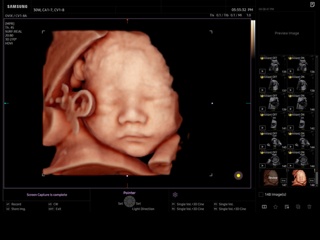

Atlas of ultrasound images - obsterics

In the section "Оbsterics" of atlas the results of ultrasonic examinations of pregnant women with different durations of gestation are represented. Here you can see images of internally organs, cerebrum, cordis and the sex of the fetus, the sonograms of multiple pregnancy, the blood flow in placenta and umbilical cord, defects of fetal`s development, etc.